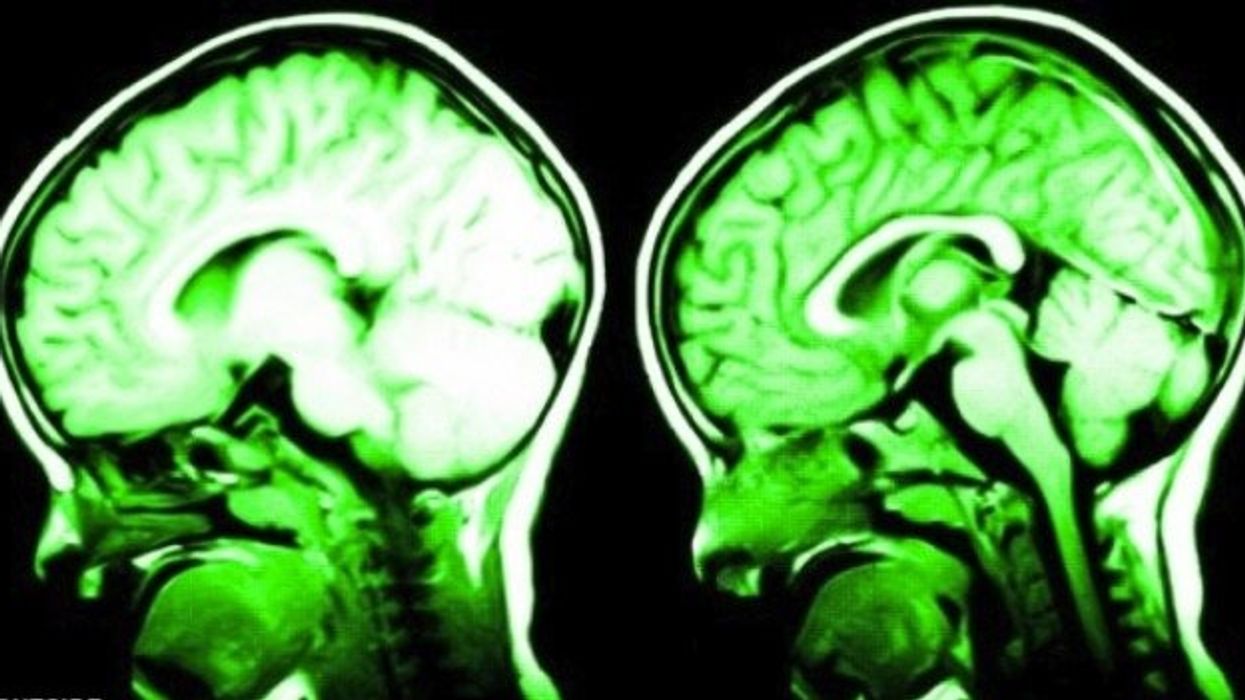

Gjërat të cilat e ndryshojnë fizikisht trurin, duke ju bërë juve më të mençur dhe pozitivë

Nëse po, atëherë kemi lajme të mira! Ekspertët kanë zbuluar disa truke të cilat mund t’i përdorni që në plot kuptimin e fjalës ta ndryshoni trurin, transmeton Telegrafi.